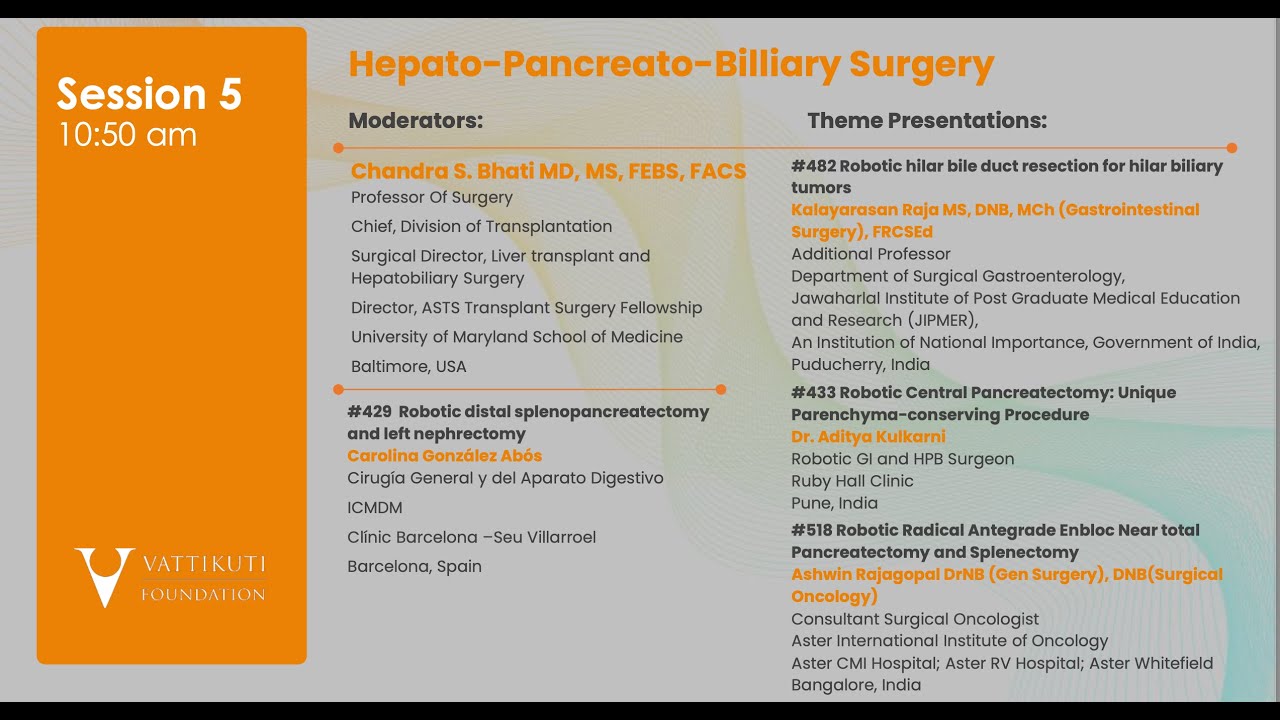

Jaipur Saturday Session 5 Hepato-Pancreato-Billiary Surgery

Humans of Robotic Surgery, KS Awards, Robotics, Surgeon, Video Library ';